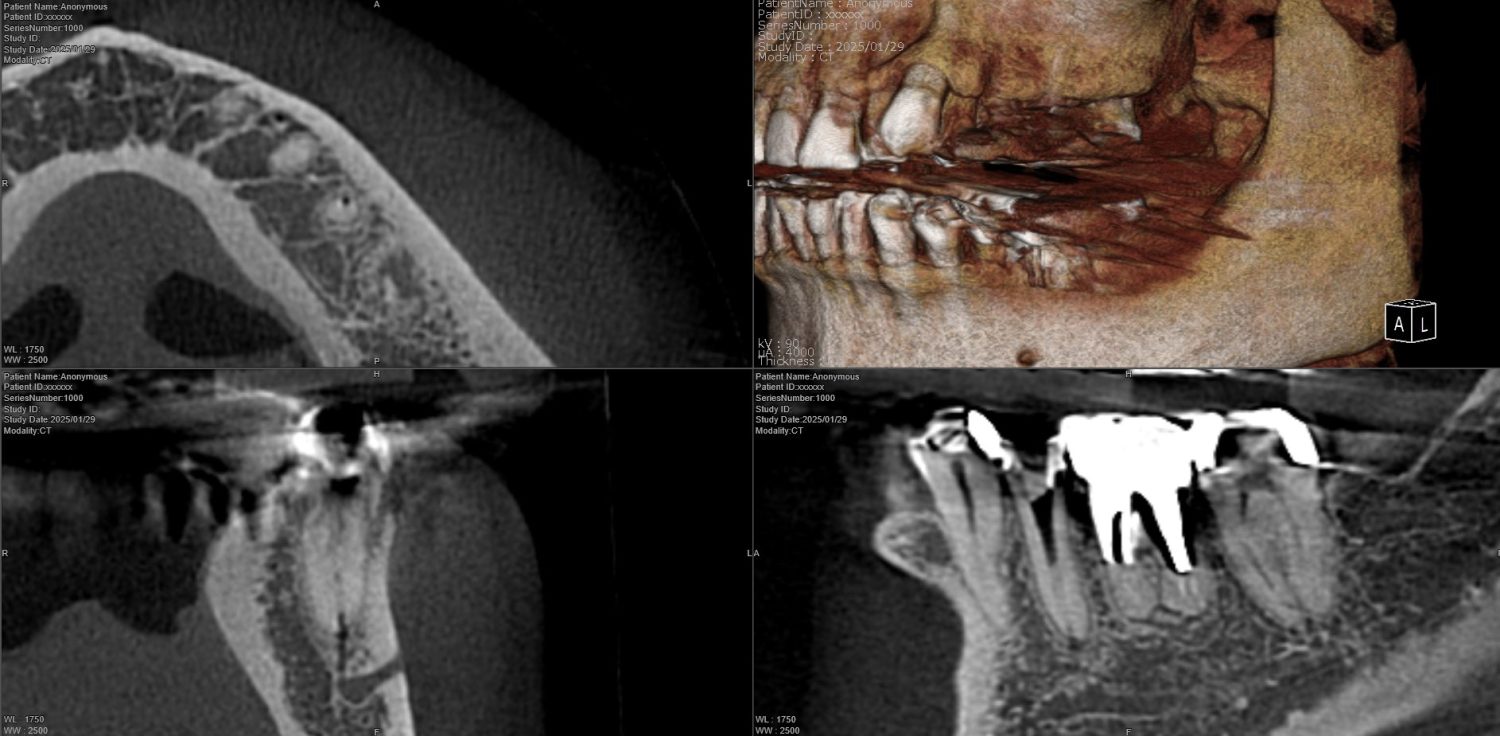

| 主訴 | 歯が折れたため来院。 |

| 治療内容 | 抜歯とともにソケットプリザベーション(歯槽骨再生療法)を行い、歯槽骨の再生を行う。その後にインプラントの埋入処置を行いました。 |

| 治療費 | ソケットプリザベーション:55,000円(税込、オプション別) オプション(エムドゲイン+ベリプラスト):49,500円(税込) インプラント埋入処置:418,000円(税込、埋入~上部構造含め) |

| 治療期間 | 9ヶ月 |

| 治療回数 | 10回 |

| 想定されたリスク | 再生療法を行っても、骨に置換されない場合もあり、その場合は追加的な処置もしくはインプラント埋入自体を断念しなければならない可能性もありました。 |